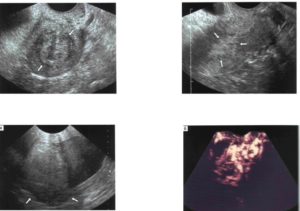

Узловые образования эндометриоза

Дополнительно, заболевание может проявляться в узловой, очаговой и диффузной форме.

Так, диффузная форма чаще всего проявляется при внутреннем типе эндометриоза.

О диффузном типе свидетельствует следующие эхопризнаки:

- круглое или овальное тело матки;

- наблюдается утолщение тканей, образующих стенку матки, чаще всего заднюю;

- тело миометрия повышенной эхогенности;

- включения на матке до 0,05 мм (отложение кальция, новообразования различного происхождения, в том числе злокачественные);

- эндометрий имеет неровный и нечеткий контур.

При узловой форме, УЗИ может показать следующее эхопризнаки:

- изменения в структуре стенке матки, чаще всего имеют округлые или овальные формы;

- в некоторых случаях видно образования, схожие на кистозные, диаметром до 30 мм;

- само образование не имеет четких контуров;

- также исследование может показать эндометриозный узел, который растет в пределах стенки матки (интерстициальный).

Очаговая форма заболевания проявляется следующим образом:

- в процессе проведения исследования УЗИ, на одном из участков мышечной стенки матки (миометрия), можно наблюдать повышенную эхогенность, с отсутствием четкого и ровного контура;

- при более дательном исследование, можно обнаружить кистозные образования от 2 до 15-16 мм;

- стенки матки могут иметь разную толщину по сравнению с друг другом.

Считается, что диагностировать очаговую или узловую форму заболевания сложнее, чем другие. Обусловлено это тем, что данные формы имеют похожие признаки и по отдельности встречаются очень редко. Чаще всего их можно наблюдать при миоме матки и диффузных поражениях.